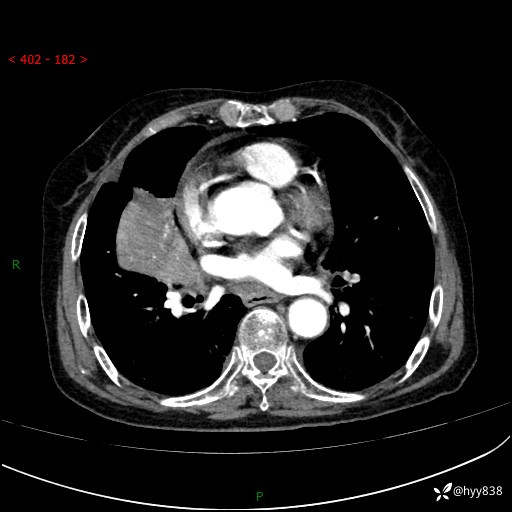

胸部CT增强(外院平扫)